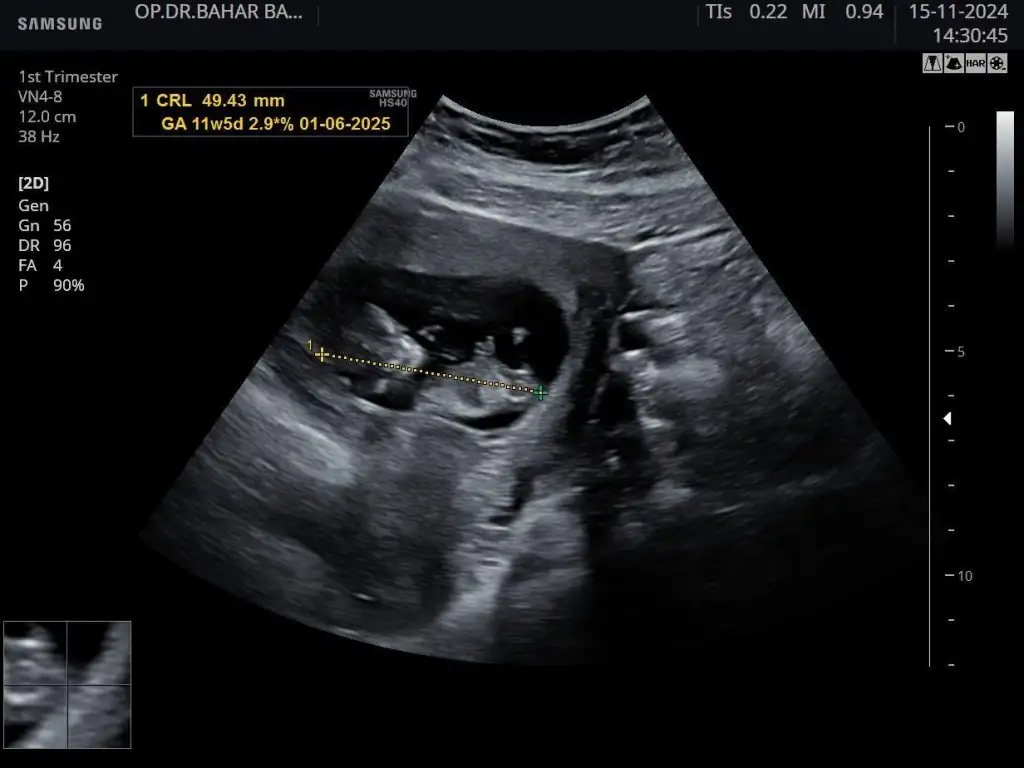

kızlar son kez cinsiyet tahminiiii

Belli değil canım ya haftaya net söyleyeceğim dedi doktorum ☺️ Yeni ultrasonlar var ama atayım bakalım yeni tahminler ne olacak ♥️

12 haftalık. Doktor bir tahminde bulundu. Kız gibi ama üstten bacak arasına da bakayım dedi üstten bir türlü göremedi. Alt popo tarafından açtı ayağını arası boş dedi. Ama daha küçük 1-2 haftaya netleşir dedi.

Merhaba 10 haftalık cinsiyet tahmini yapabilir misiniz rica etsem